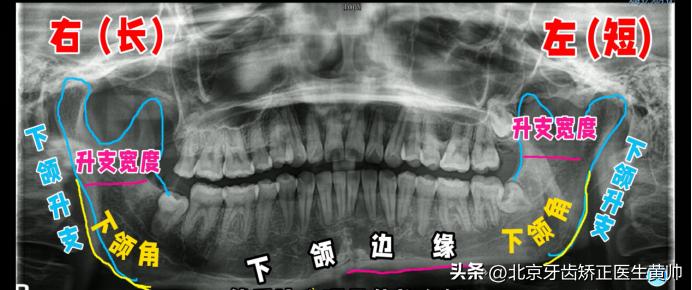

2、曲面断层片

曲面断层片主要看这几个信息:下颌升支的长度、下颌升支的宽度、下颌角的形态。

◆ 下颌升支的长度、宽度是否一致

通常来说我们下颌升支的长度、宽度是基本对称的,视觉上不会存在明显不对称问题。

如果说两侧下颌升支的长度、宽度不一致的问题,那就非常有可能会出现大小脸的情况。

例如这个患者,他右边的下颌升支要长一点,左边的则要稍微短一点。

◆ 下颌角的形态是否一致

从片子上看下颌角双侧发育是不是对称的,以及下颌边缘是否在同一高度。

图中的患者,他的左侧、右侧明显没有在一个水平面上。

所以,如果你的片子当中存在下颌升支的长度、宽度不一致,包括你的下颌角形态发育不对称、下颌边缘线不在一个水平面的问题,这都提示你的大小脸是有骨性因素的。